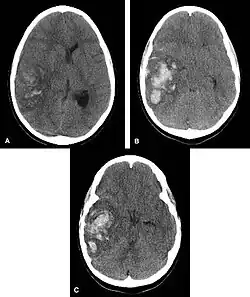

Multiple intraparenchymal hemorrhage

Hemorrhagic neoplasms are more complex, heterogeneous bleeds often with associated edema. These hemorrhages are related to tumor necrosis, vascular invasion and neovascularity. Glioblastomas are the most common primary malignancies to hemorrhage while thyroid, renal cell carcinoma, melanoma, and lung cancer are the most common causes of hemorrhage from metastatic disease.